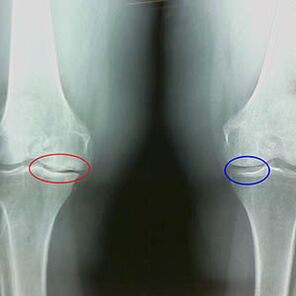

Determination of the degree of arthrosis occurs by x -rayrevealing participation in the pathological process of bone structures.Their change indicates that the muscle system has been in an imbalance for 5-10 years.As a rule, peopleFor several years they experience aching pains.

At the first stage of arthrosis, which is detected by accident, a slight increase in bone spurs occurs.The growths appear in places of the greatest instability of the joint.Typically, patients rarely experience pain or discomfort during movement.

The second stage of arthrosis is considered easy.The radiograph reveals significant bone spurs, but the cartilage is not affected.The amount of synovial fluid is reduced, but symptoms of pain appear after long walking and running, stiffness in the joint and soreness when bending and in the position on the knees.

Early X -ray features of the second stage of knee arthrosis:

- the pointed edges of the inter -crib tubercles on the tibia, where the cross -shaped ligament is attached;

- narrowing of the joint gap on the medial side;

- The pointed edges of the condyles of bones on the medial sides, less often in lateral - depending on the development of the valgus or varior joint deformation.

For the second stage in LarsenThe narrowing of the joint gap by more than 50% is characteristic, but this can only be checked in dynamics or comparison with an unlikeed joint.

The radiograph shows the presence of osteophytes, a change in the space between the femoral and tibia bones, which indicates the loss of cartilage in the knee.Sometimes the x -ray of the knee joints shows significant signs of cartilage wear, but patients do not experience significant pain.On the contrary, arthrosis of the first stage can disrupt the function of the knee, since the cause of pain is hypotonic muscles.